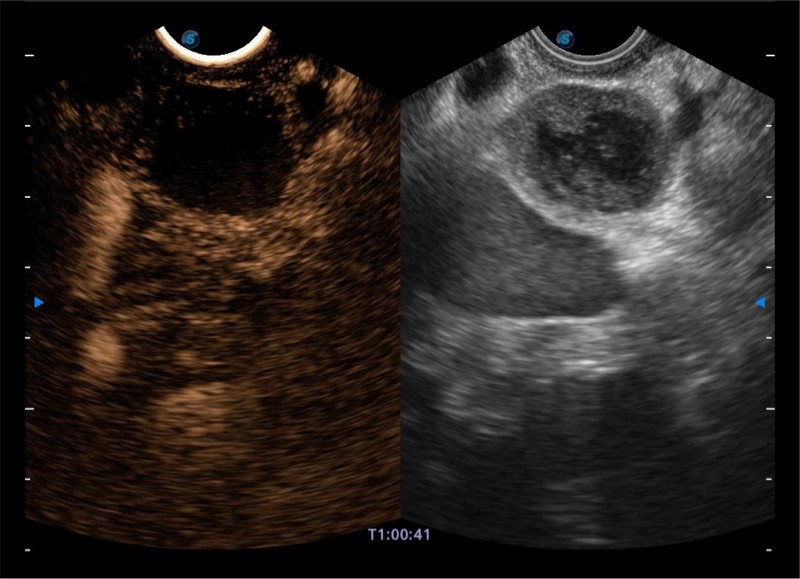

搭载百万级CMOS成像技术

及自主研发凸阵换能器,

可呈现优质的内镜和超声画面

基于二十年的超声技术积累,乐玩lewin国际提供了最新一代的独立超声主机,在提供高质量图像的同时满足多学科使用。具备常见多普勒技术并提供弹性成像、声学造影等高端影像技术。新一代传感器具有更强的抗干扰能力并减少图像伪影。

4-12MHZ宽频输出